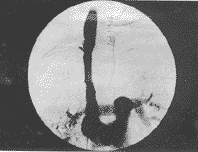

12例中完全性阻塞8例(图1),4例明显狭窄,狭窄程度均>85%(图3),有2例有瘤栓(图3),5例有血栓形成表现为充盈缺损,侧支血管较多。狭窄段长约4~10cm。

图1肺癌致上腔静脉闭塞,上腔静脉侧支循环形成。